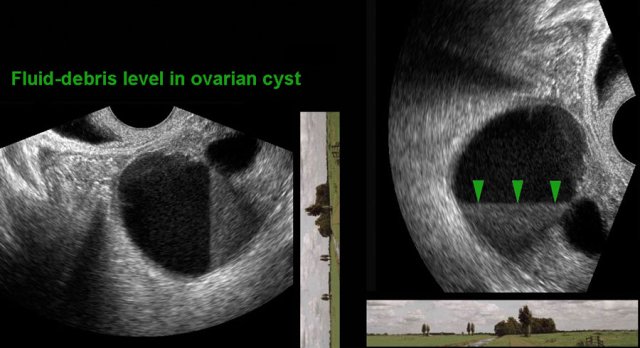

Probe orientation in TVUS Probe orientation in TVUS

Most sonographers, however,  look at the TVUS image rotated 90  degrees anti-clockwise, as in the right panel.

This is not necessarily a problem, as long as one realizes the different presentation of the anatomy, including gravity effects.

Note the horizon in relation to the TVUS image.

Fluid-debris-level in endometriotic cyst Fluid-debris-level in endometriotic cyst

For instance, in this patient with an endometriotic cyst the fluid-debris-level is vertically oriented, and could therefore be misinterpreted.

This could be overcome by clockwise rotating the US image 90 degrees (right image).